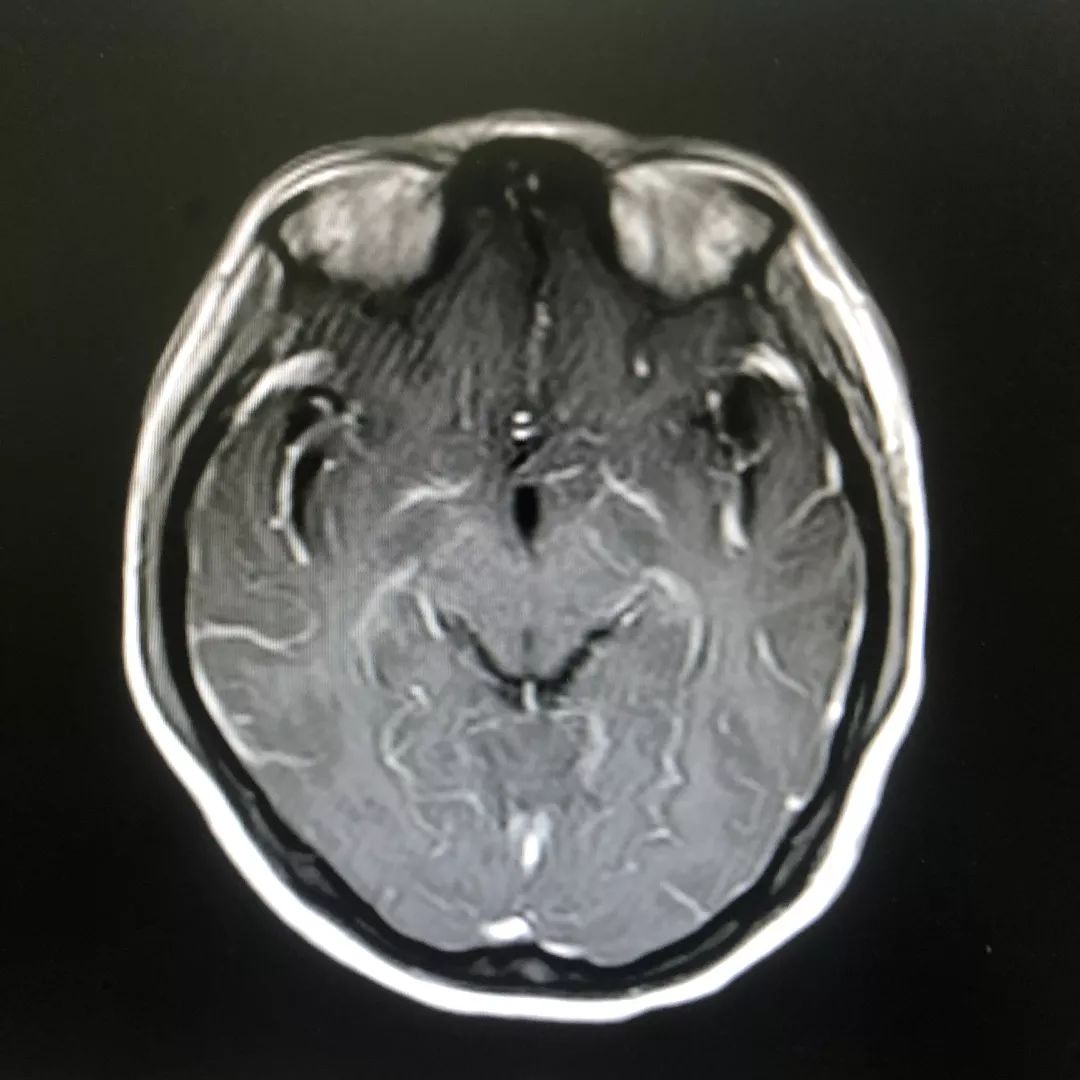

头颅增强磁共振:脑膜多发线样增强影